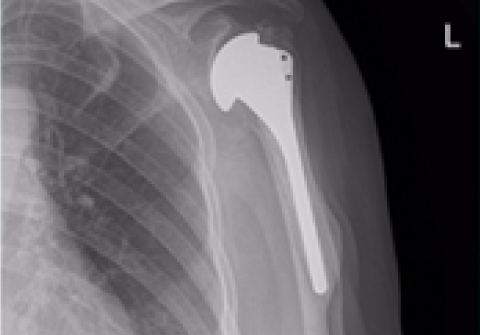

전방도달 최소 침습 고관절 인공관절수술

(직접전방도달법, direct anterior approach)

수술 후 빠른 회복

□ 입원 기간 28% 감소

□ 수술 후 통증 58% 감소

□ 진통제 사용률 31% 감소

더 적은 수술 위험

□ 감염률 45% 감소

□ 최소 절개

□ 수술 후 탈구율 35% 감소

□ 재수술률 16% 감소

더 높은 환자 만족도

□ 수술 후 첫 3개월 만족도가 타 방법에 비해 높음

□ 미국 인공관절 전문의 90% 이상이 원하는 수술 방법 (2018년 전 미 무릎, 고관절 전문의 대상 설문조사 AAHKS)

고관절 인공관절 전체치환술

2016.09.26

2017.01.24

고관절 인공관절 부분치환술

2016.10.07

2017.02.09